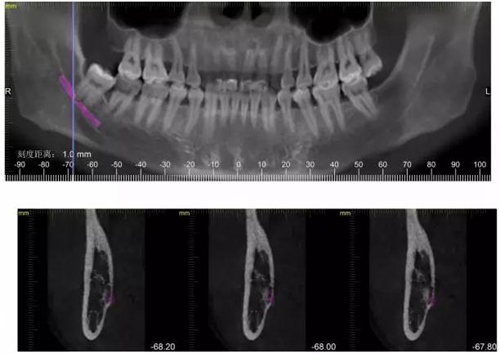

檢查:48號牙稍偏近中生長,周圍牙齦稍白,遠(yuǎn)中齦袋中有少許滲出物,探診;未出血,叩(--),冷熱(--)。47遠(yuǎn) 中未見齲壞,47冷熱(--)叩(--)。舌側(cè)少許齦上結(jié)石。X線檢查,48遠(yuǎn)中有陰影約2mm,根尖在神經(jīng)管內(nèi)約2--3mm。根尖未見陰影。

下面CBCT,可以看到兩個牙根的根尖三分之一在神經(jīng)管里面。

CBCT神經(jīng)管標(biāo)線,可以看到標(biāo)線不能連續(xù),中間被阻斷。